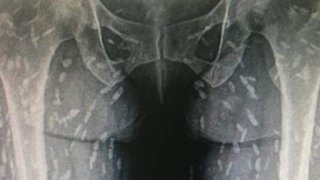

น่ากลัวมาก! เผยภาพฟิล์มเอกซเรย์คนไข้ เห็น "พยาธิตัวตืด" กระจายทั่วตัว "อ.เจษฎา" แนะคนกินของดิบควรงด